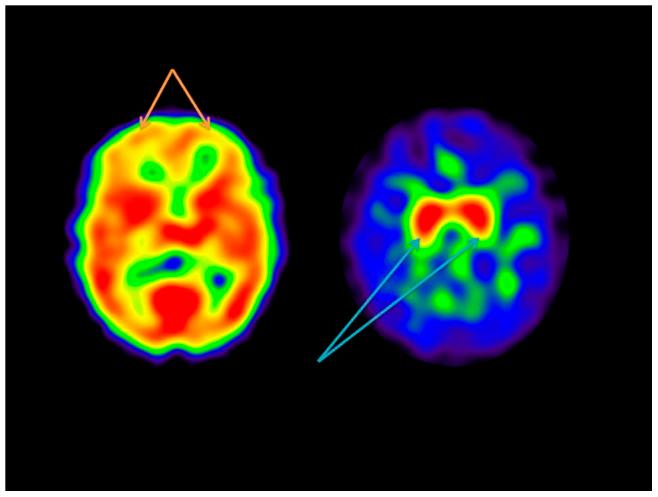

Clinical comparison of 99mTc exametazime and 123I Ioflupane SPECT in patients with chronic mild traumatic brain injury.

This study evaluated the clinical interpretations of single photon emission computed tomography (SPECT) using a cerebral blood flow and a dopamine transporter tracer in patients with chronic mild traumatic brain injury (TBI). The goal was to determine how these two different scan might be used and compared to each other in this patient population.

Twenty-five patients with persistent symptoms after a mild TBI underwent SPECT with both (99m)Tc exametazime to measure cerebral blood flow (CBF) and (123)I ioflupane to measure dopamine transporter (DAT) binding. The scans were interpreted by two expert readers blinded to any case information and were assessed for abnormal findings in comparison to 10 controls for each type of scan. Qualitative CBF scores for each cortical and subcortical region along with DAT binding scores for the striatum were compared to each other across subjects and to controls. In addition, symptoms were compared to brain scan findings. TBI patients had an average of 6 brain regions with abnormal perfusion compared to controls who had an average of 2 abnormal regions (p<0.001). Patient with headaches had lower CBF in the right frontal lobe, and higher CBF in the left parietal lobe compared to patients without headaches. Lower CBF in the right temporal lobe correlated with poorer reported physical health. Higher DAT binding was associated with more depressive symptoms and overall poorer reported mental health. There was no clear association between CBF and DAT binding in these patients.

Overall, both scans detected abnormalities in brain function, but appear to reflect different types of physiological processes associated with chronic mild TBI symptoms. Both types of scans might have distinct uses in the evaluation of chronic TBI patients depending on the clinical scenario.